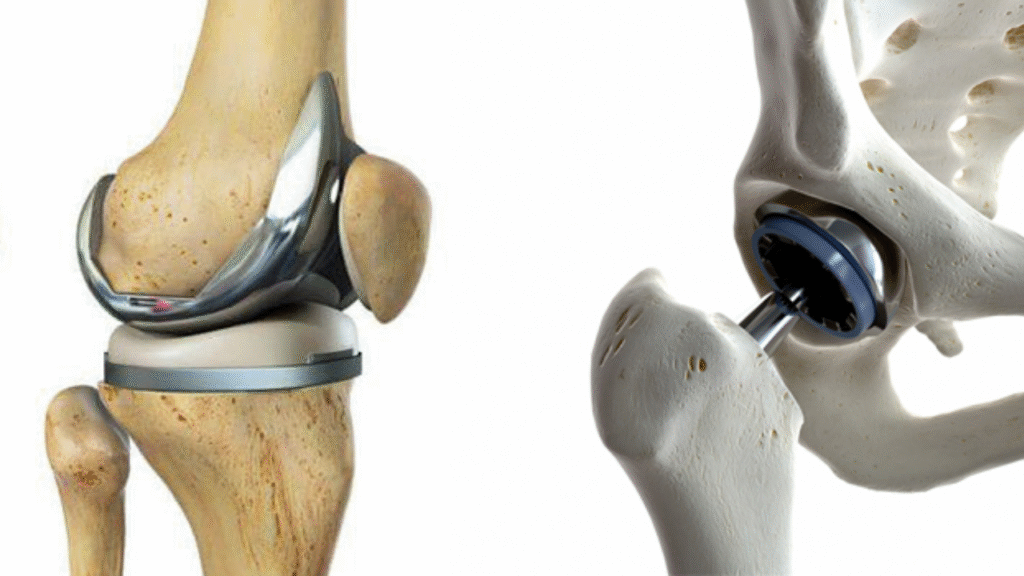

Joint Replacement Surgery is a procedure where damaged parts of a joint—such as the hip, knee, or shoulder—are replaced with artificial implants to restore movement and relieve chronic pain. It is often recommended for patients with arthritis, joint injuries, or long-term wear and tear.

Joint Replacement Surgery is a highly advanced orthopedic procedure used to relieve pain and restore function in joints that are severely damaged by conditions like osteoarthritis, rheumatoid arthritis, post-traumatic injuries, or degenerative diseases. It involves replacing the damaged joint surfaces with artificial implants designed to mimic natural movement and improve quality of life.

This procedure is most commonly performed on the hip, knee, and shoulder joints, which bear significant stress from daily activities. When conservative treatments such as medications, physical therapy, or injections fail to relieve chronic joint pain, joint replacement becomes a reliable and long-term solution.

Hip Replacement (Total Hip Arthroplasty): Replaces the ball and socket of the hip with metal, ceramic, or plastic implants.

Knee Replacement: Involves resurfacing the ends of the femur and tibia to restore smooth movement and alignment.

- 1. Removal of the damaged bone and cartilage from the affected joint (hip, knee, or shoulder)

- 2. Preparation of the surrounding bone to support the implant.

- 3. Implantation of prosthetic components, usually made of metal, ceramic, or plastic, designed to mimic natural joint function.

- 4. Precise alignment and fixation of the implant for smooth, pain-free movement.